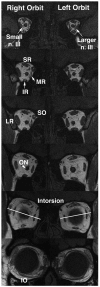

Magnetic resonance imaging demonstrates neuropathology in congenital inferior division oculomotor palsy

Isolated inferior division oculomotor nerve palsy (ONP) is rare VSports手机版. Acquired cases have been associated with neurologic or systemic disease. To our knowledge, congenital inferior division ONP is previously unreported. We present a case of congenital inferior division ONP in which magnetic resonance imaging demonstrated the structural neuropathy. .